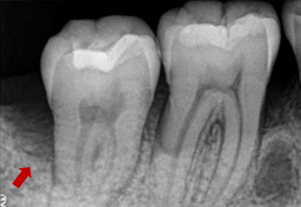

症例3(再生療法)

Before

After

- POINT

- 他院で歯周病の治療をしていましたが、なかなか歯周病が改善されず、セカンドオピニオンにて来院された患者様です。歯周病の進行した部分に再生療法を行い(エムドゲインを使った歯茎の手術)ホームケアを徹底することで改善されました。

今後も継続したメインテナンスが必要です。